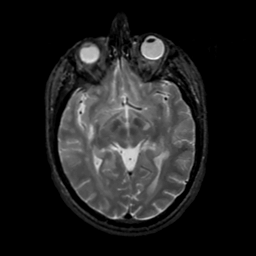

MR Study #7, March 24, 1991 -- Slice #22